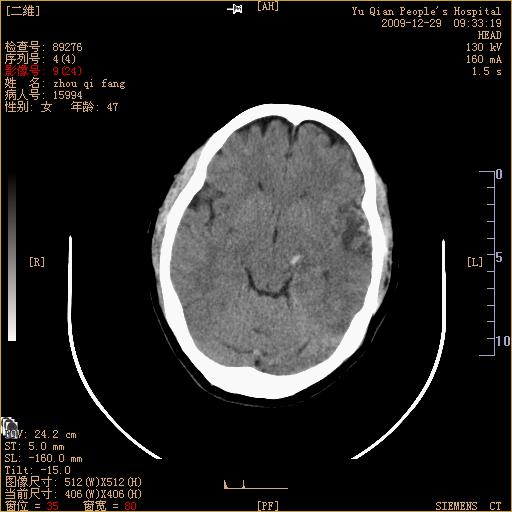

头部外伤后1天   请看看左侧丘脑外侧原是否为小血肿?(两天表现大致相仿。)谢谢

左颞叶前外部见片状挫裂伤,左丘脑小血肿;颅板下见多发小片状血肿影,两侧额部见少量蛛网膜下腔出血,

左额叶颅内板下也有一高密度灶。。。考虑多发小灶性出血(挫裂伤)。。。复查后再定

不好定。同时左侧裂池形态异常,左侧豆状核点状高密度,第四幅右额叶稍高密度影,最后一幅左额叶颅骨内板下方小片状高密度影。复查。